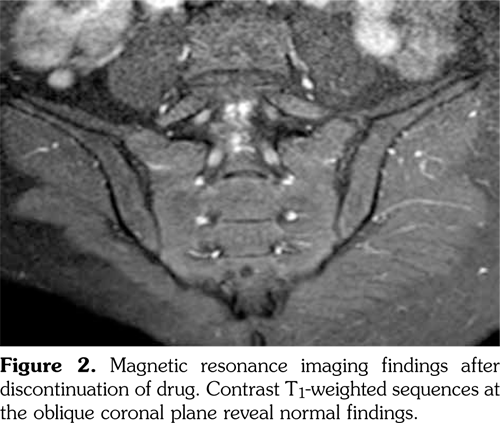

Physical examination revealed limited and painful lumbar movements in all directions. Modified Schober’s test was measured as 19 cm, while fingertip to floor distance was measured as 5 cm. There was full range of motion in hip joint, however, hip movements were painful. Chest expansion, sacroiliac provocation tests (mennel, gaenslen), and neurological examination findings were normal. Tinnel’s sign and Phalen’s maneuver were negative. Thus, the underlying origin of the back pain was considered to be inflammatory, and laboratory tests were performed. Laboratory analysis demonstrated normal biochemical values and complete blood count. Acute phase reactants including C-reactive protein and erythrocyte sedimentation rate were 3 mg/L (normal range: 0-3 mg/L) and 1 mm/h (0-15 mm/h), respectively. Urinalysis was normal. Serum vitamin B 12 and folic acid levels, thyroid function tests, and parathyroid hormone levels were within normal range. Hepatitis panel, including hepatitis B surface antigens, hepatitis B surface antibodies, hepatitis C virus antibodies, and human immunodeficiency virus antibodies, was negative. Serological evaluations including anti-cyclic citrullinated peptide and anti-nuclear antibody tests were negative. In addition, rheumatoid factor test was also negative. Spinal magnetic resonance imaging (MRI) was considered to be normal. However, sacroiliac MRI showed bilateral bone marrow edema and subchondral sclerosis (Figure 1 and Figure 2). Nerve conduction studies and electromyography revealed sensorimotor demyelinating polyneuropathy (Table 1 and Table 2).

Acne fulminans is a component of SAPHO syndrome (acronym for Synovitis, Acne, Pustulosis, Hyperostosis and Osteitis). In SAPHO syndrome, constitutional symptoms, abnormal laboratory findings and musculoskeletal symptoms are observed as well as necrotizing acne. Sacroiliitis was detected in 21% of the patients having acne fulminans in association with arthritis. In addition, development of sacroiliitis after systemic isotretinoin treatment was also reported in patients with SAPHO syndrome.(15,16) Dinçer et al.(17) reported sacroiliitis development in three patients aged 18-25 years who used 15-25 mg/day isotretinoin for a time period ranging from three months to two years. Unilateral sacroiliitis developed in patients who used isotretinoin for three months while bilateral sacroiliitis developed in patients who used isotretinoin for two years. Human leukocyte antigen B27 (HLA-B27) positivity was detected in one of three cases. Ekşioğlu et al.(3) also reported bilateral sacroiliitis and demyelinating polyneuropathy in a patient 20 years old, who used isotretinoin for three months (30 mg/day during first two months and 40 mg/day during last month). HLA-B27 positivity was detected in this case. Our patient was 25 years old and used isotretinoin for six months (20 mg/day during first three months and 40 mg/ day during last three months). Sacroiliitis developed bilaterally in our case. Sacroiliitis in our case was linked to isotretinoin use, as the patient had no musculoskeletal complaint prior to isotretinoin use. Furthermore, hip pain, back pain and active sacroiliitis findings on MRI emerged three months after prescription of isotretinoin. Complaints and active sacroiliitis findings on MRI disappeared two months after withdrawal from drug.